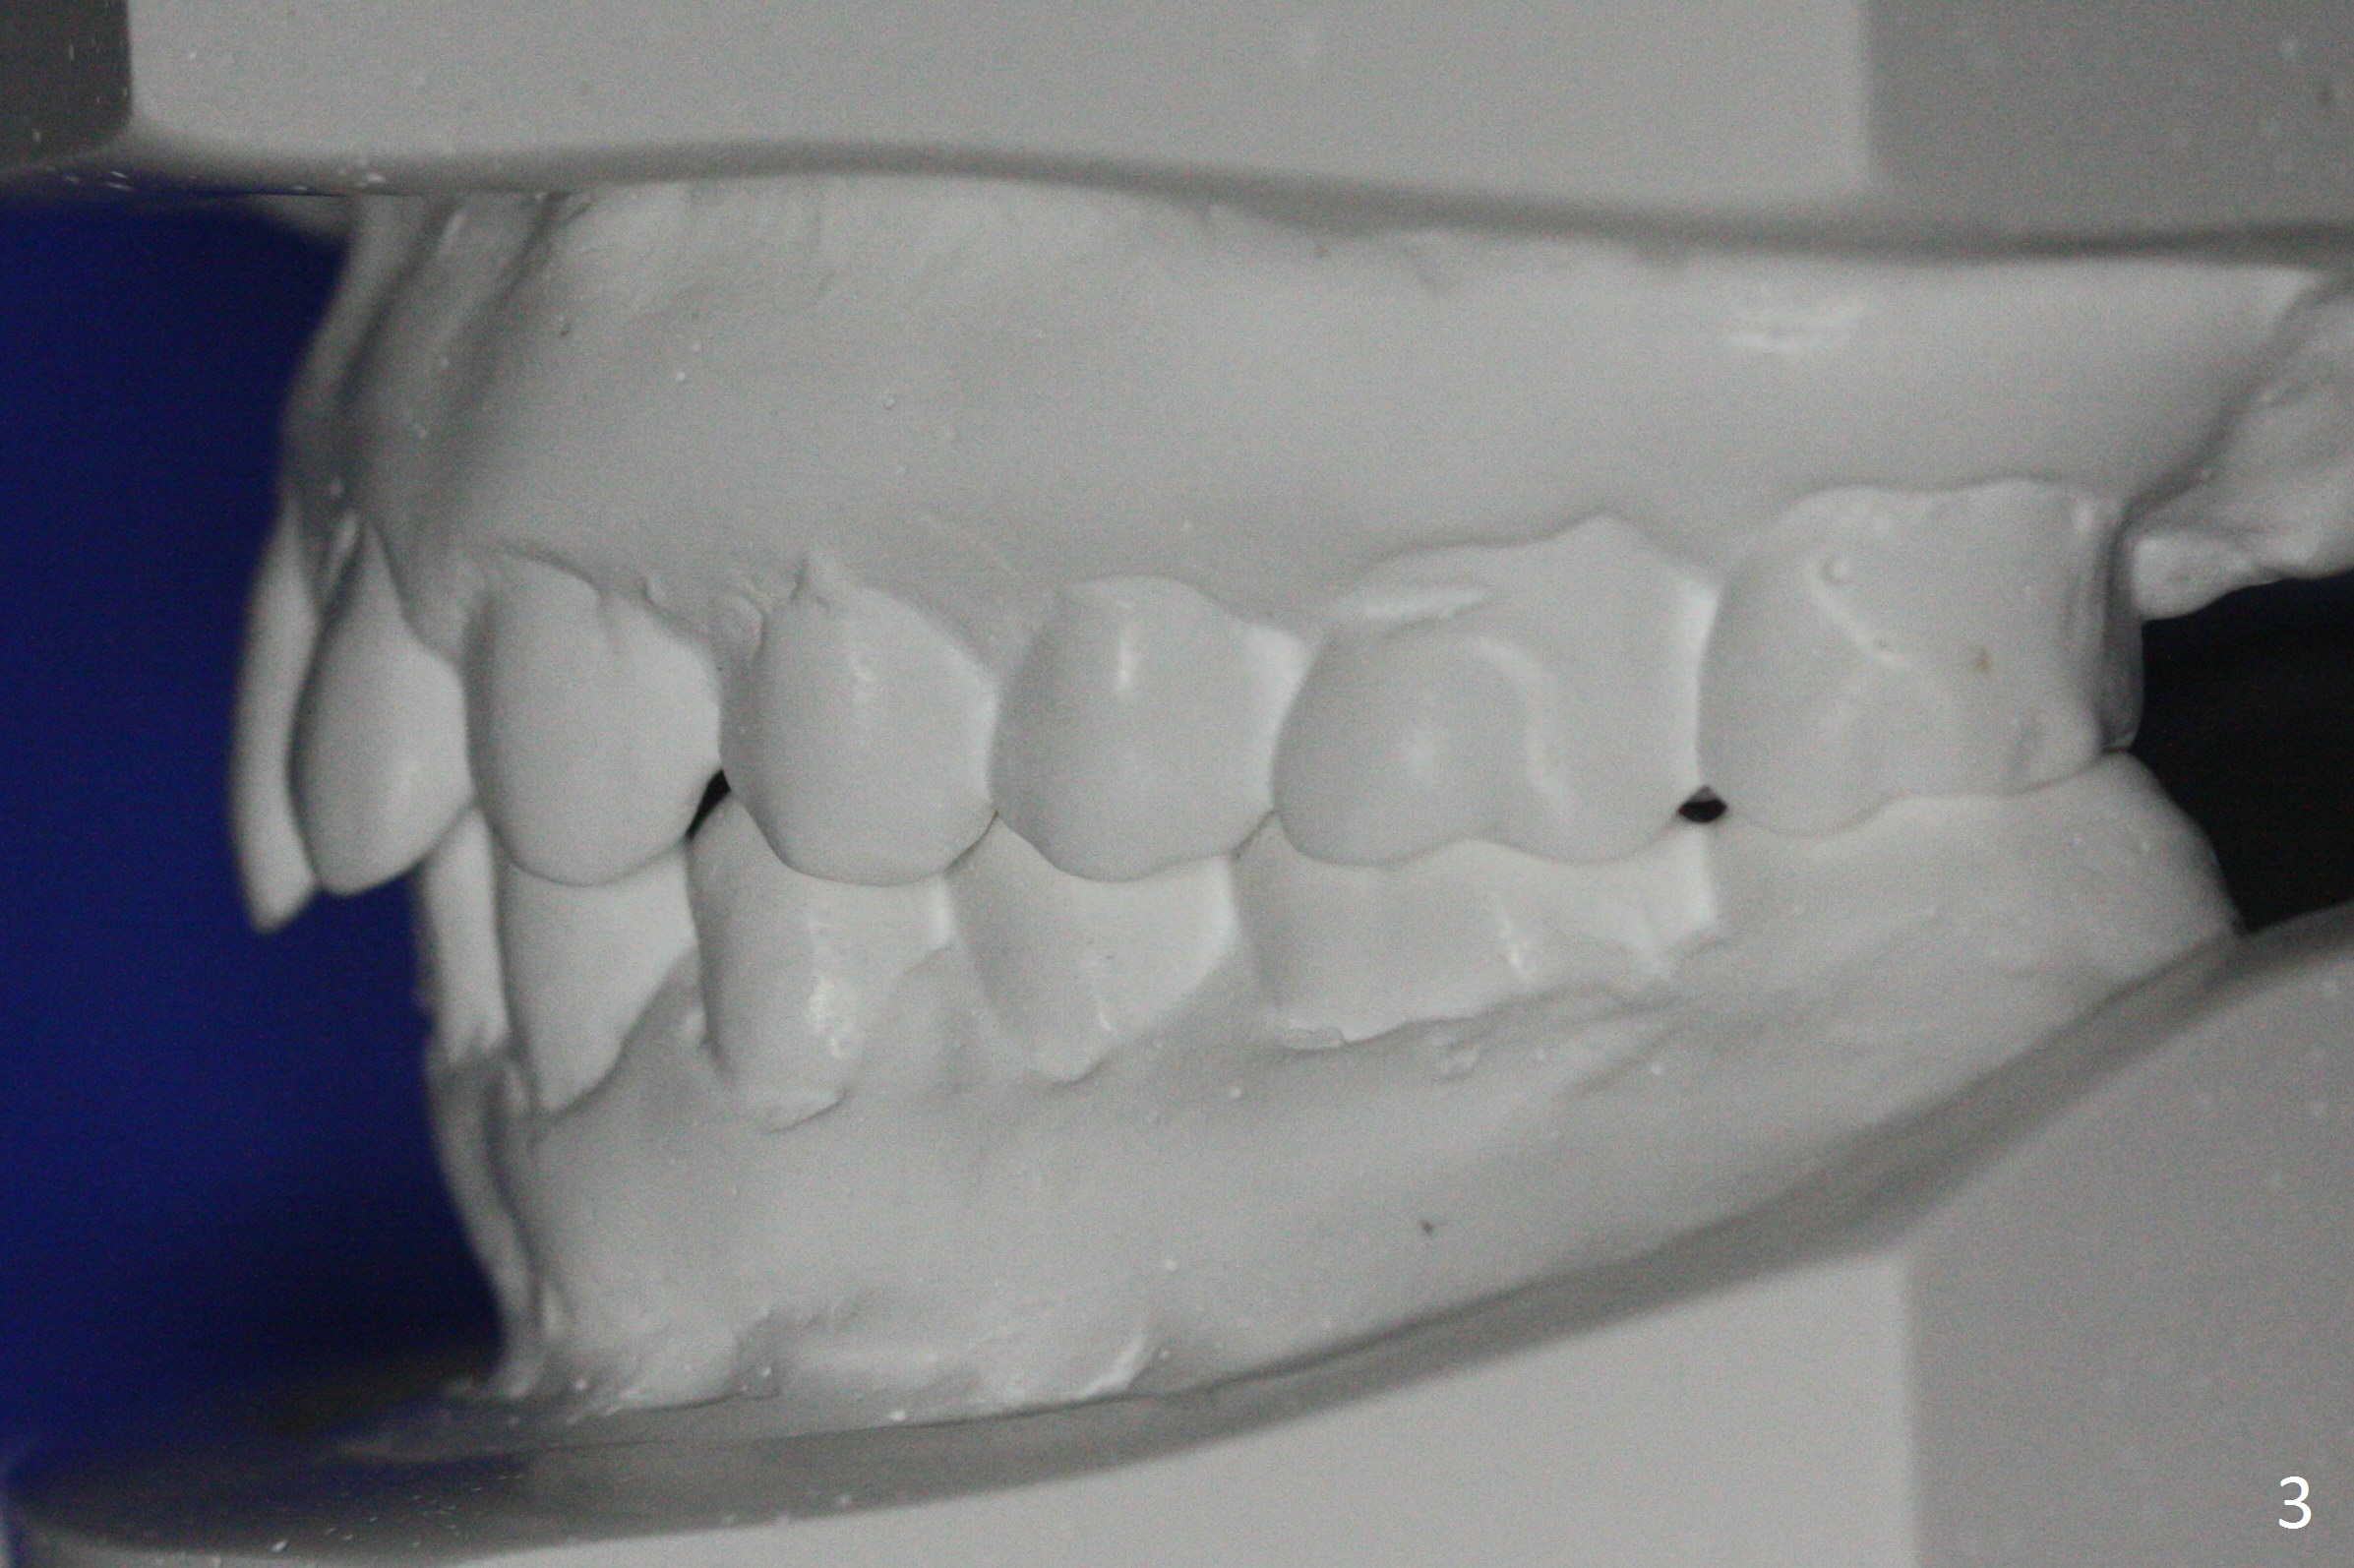

When orthodontic treatment is finished for a patient with crowding and anterior deep bite in 13 months, a diastema is found between the upper central incisors (Fig.2), which could be prevented by applying power chains for a few appointments prior to debanding. The upper anterior teeth look protrusive (Fig.4), proximal reduction seems necessary. Taking impression prior to debanding may reveal deficiency (Fig.5,6; 2nd good practice). The hidden diastemata can be revealed by use of 3-way syringe. The only prominent change is the reduction in the anterior deep bite (Fig.7,8 (posterior view)).